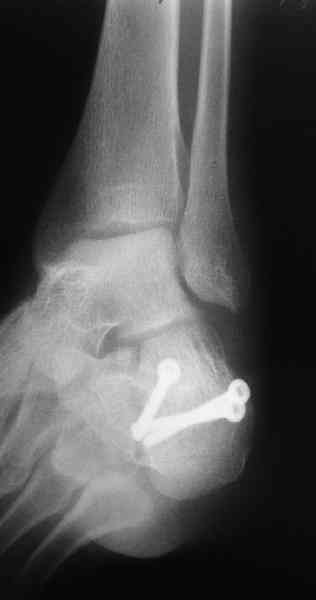

Пяточной пластиной

С уважением, А.Семенистый.

ГКБ № 13, Москва.

Какой предпочитаете доступ? Нет ли показательных рентгенснимков?

Открытый и закрытый способы лечения.

MOST OF MY COLLEGUES WOULD OPEN IT LATERALLY( a flap) and having a proper reduction would put a plate.

Фиксации спицами для спокойного сна хирурга пожалуй достаточно. А для пациента?